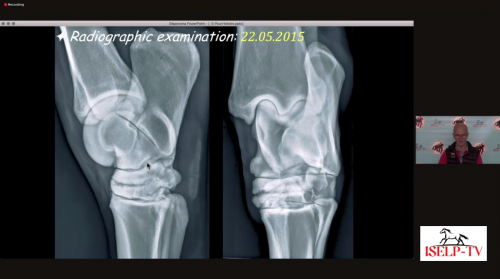

3:15pm - Dr. Kurt Selberg - Presentation - "Improving Radiology of The Hock"